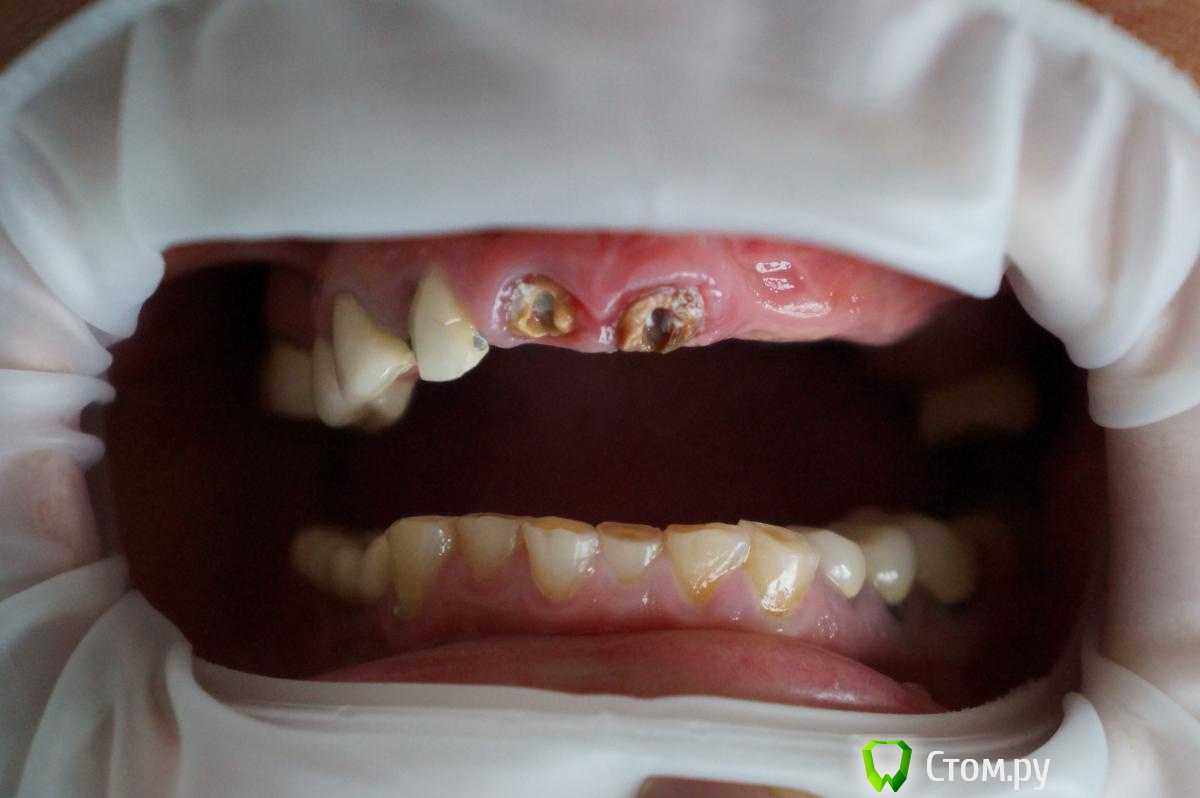

Брат 2 Опубликовано 15 ноября, 2013 Поделиться Опубликовано 15 ноября, 2013 Уважаемые коллеги планирую очередное тотальное вмешательство. Ссылка на комментарий

Брат 2 Опубликовано 15 ноября, 2013 Автор Поделиться Опубликовано 15 ноября, 2013 На в/ч планирую оставить 1.3 1.4 1.6 для мостовидного протеза, импл в позицию 1.2,второй сегмент синус+ 4 импл в позиции 2.3 2.4 2.5 2.6, мост протез 1.2-2.6,На н/ч установил 3 импл с врем. Сходятся ли наши мнения? )) Ссылка на комментарий

viruzzz Опубликовано 15 ноября, 2013 Поделиться Опубликовано 15 ноября, 2013 а с низом что дальше? выраженная стираемость зубов, уменьшение межальвеолярной высоты...я бы предпочел имплантацию в позициях 12-22-24-26если 12 действительно надо удалять... Ссылка на комментарий

Брат 2 Опубликовано 15 ноября, 2013 Автор Поделиться Опубликовано 15 ноября, 2013 Низ полностью после верха. 2.2 отсутствие объёма кости. На счёт удаления 1.2 1.1 2.1 пока не решил, поэтому и создал тему. Арки по нисходящей от центральных к жевательным, если удалю ещё выше подскочат и зенит 1.2 будет намного выше 1.3 Хотелось бы обойтись без удалений. Длина резцов останется приемлемой. Мне кажется переход между 2.1 и 2.2 будет меньше заметен. Губа при улыбке в области 2 сегмента гораздо ниже. В понедельник будет КТ. Станет чуть яснее. Ссылка на комментарий

Брат 2 Опубликовано 16 ноября, 2013 Автор Поделиться Опубликовано 16 ноября, 2013 Тогда уже 23, 25 и 26, чтобы сохранить адекватное расстояние между платформами. А лучше сделать шаблон и отправить с ним на КТА что скажете по поводу удаления резцов? Ссылка на комментарий

Pavluha Опубликовано 23 ноября, 2013 Поделиться Опубликовано 23 ноября, 2013 Я бы не стал устанавливать имплантаты в данной ситуации.Прежде всего - жесткая каппа на верхнюю челюсть с разобщением 2-4 мм - 6 месяцев минимум. Закрепление высоты на временных ч/с верх и низ + временные коронки на оставшиеся зубы. Санация полости рта. Установка имплантатов. Протезирование. Ссылка на комментарий